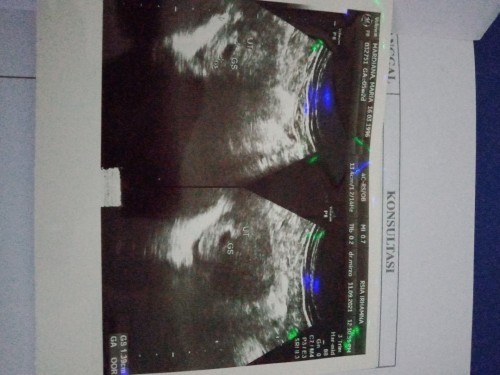

Hasih USG 5W

Pernah punya pengalaman buruk saat hamil anak pertama, alhamdulillah sekarang diberi gantinya lg๐ Tau hasil tespek positif, langsung USG buat mastiin bener hamil / gk Dan ternyata sudah terlihat kantung mungil nya si calon buah hati๐ nyaman bngt ketemu dokternya detailโบ๏ธ Doain ya bunda" supaya selalu sehat kuat ๐#bantusharing